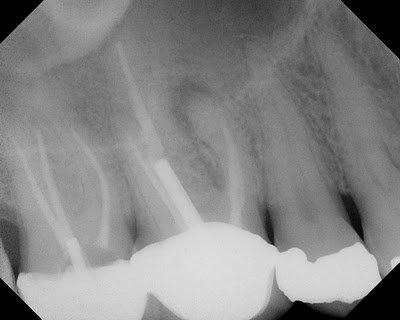

This patient presented for evaluation. The teeth are asymptomatic, but a lesion seen by his general dentist. The lesion is obviously on the MB root of #3, with ledged MB canal. The crown margins looked good and since the MB canal is ledged, we were planning to treat this tooth with an apicoectomy. I recommended a routine, pre-surgical CBCT to evaluate the root anatomy, sinus proximity and buccal bone contours.

This slice through the MB root shows that there is a missed MB#2 canal.